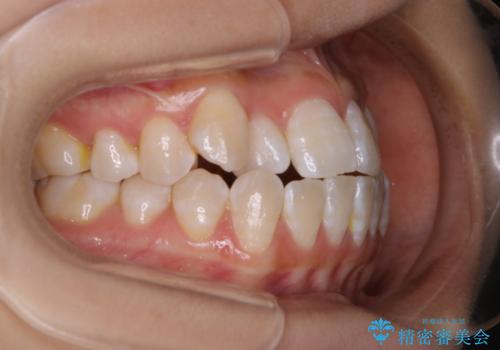

前歯のがたつきとオープンバイト:インビザラインでまとめて治す

- 噛み合わせと、前歯のがたつきが気になるとご相談にいらした方です。インビザラインFULLで綺麗な歯並びと噛み合わせを作ることが出来ました。

オープンバイトの方への治療は、通常抜歯を行いワイヤーによる矯正治療を行うことが多いですが、今回はインビザラインの特性を生かし、非抜歯にて綺麗な歯並びを作ることが出来ました。